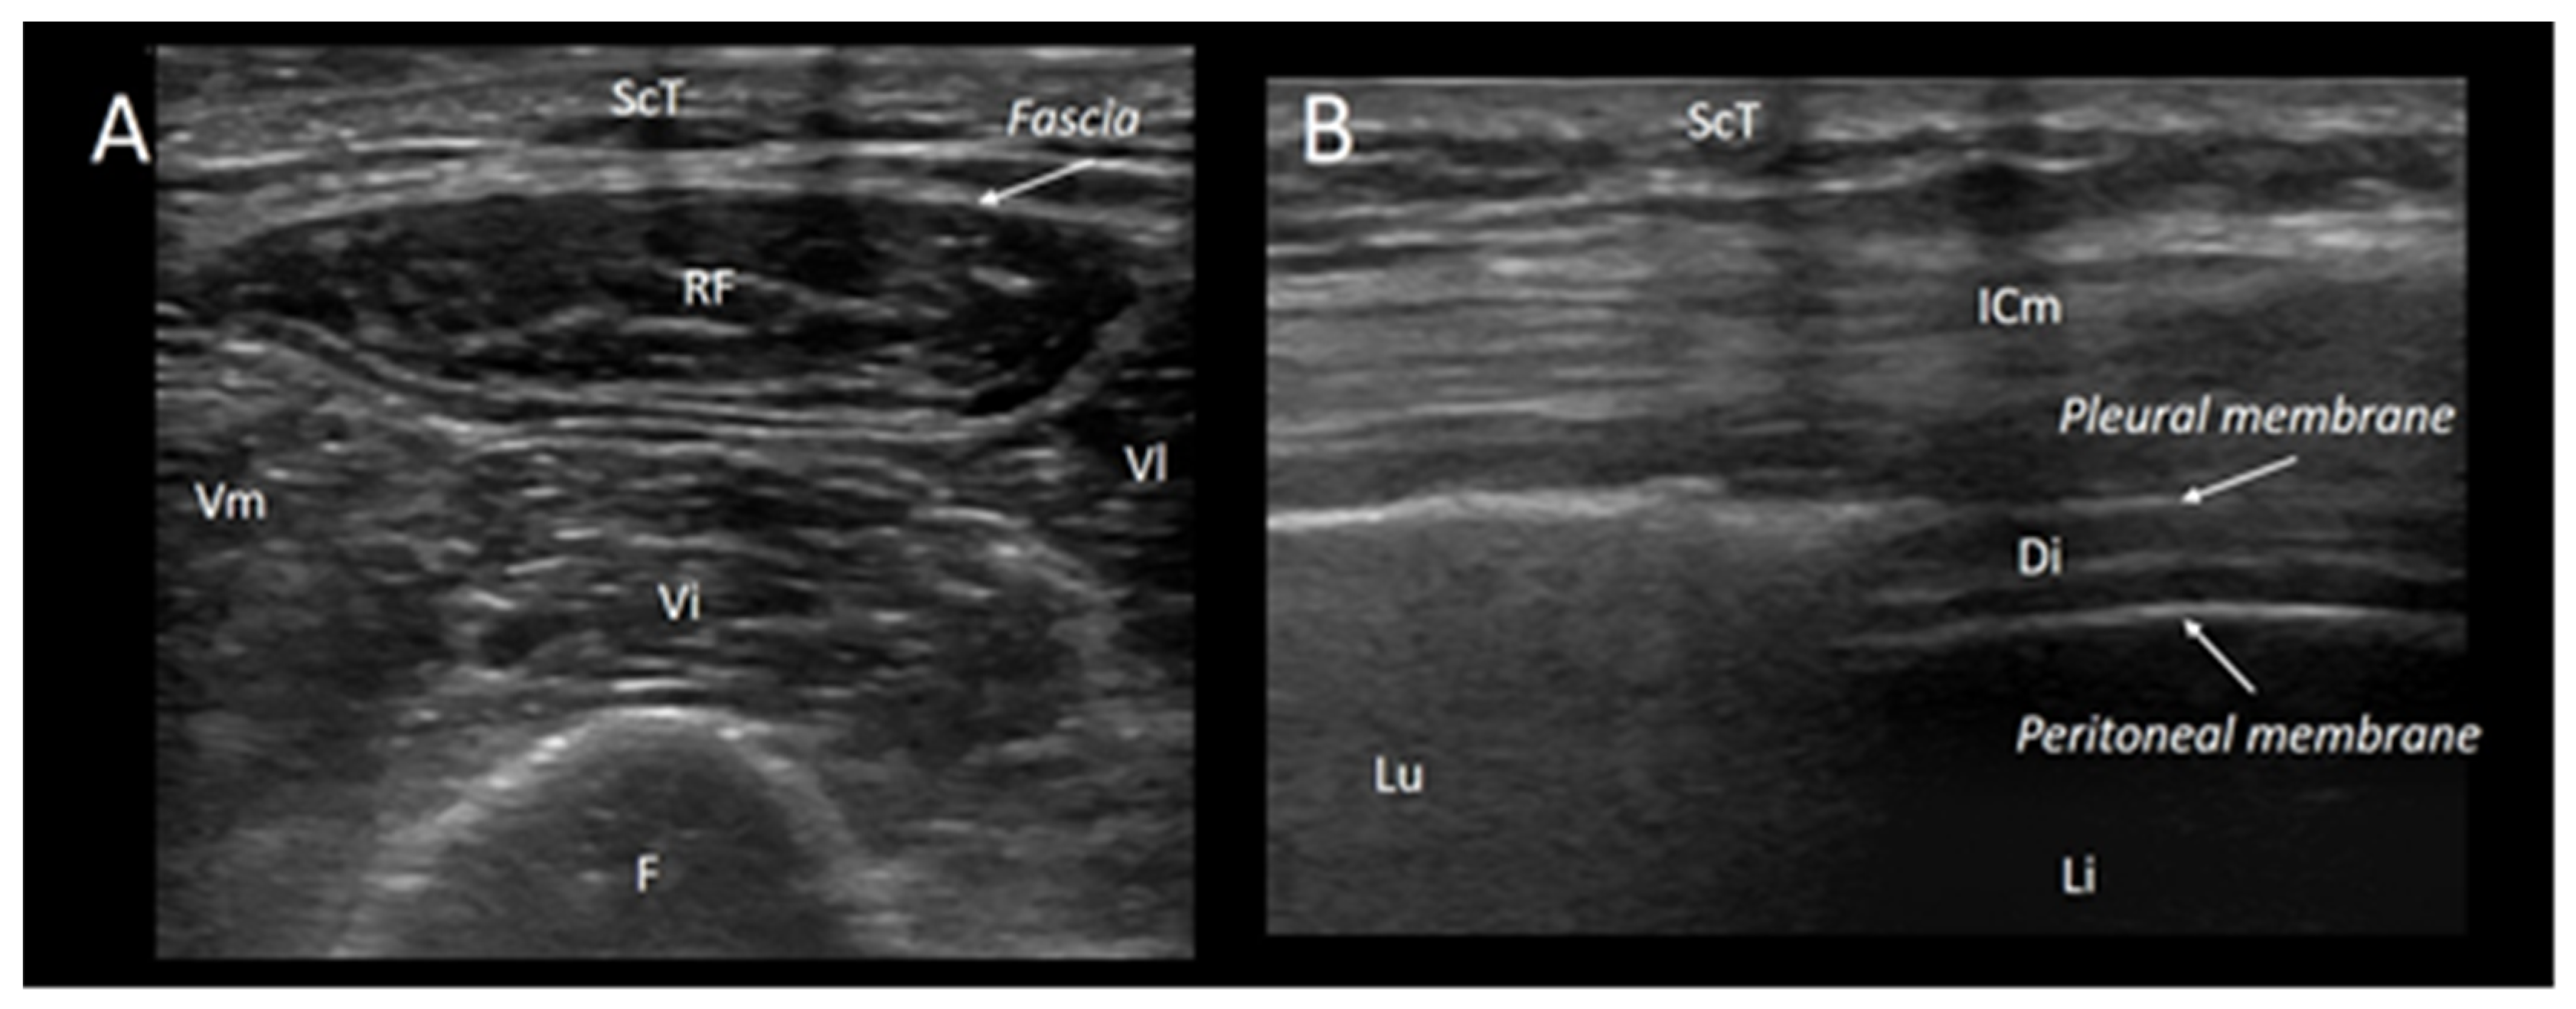

- Pillen, S.; Boon, A.; Van Alfen, N. Muscle ultrasound. Handb. Clin. Neurol. 2016, 136, 843–853. [Google Scholar]

- Kim, S.Y.; Cheon, J.H.; Seo, W.J.; Yang, G.Y.; Choi, Y.M.; Kim, K.H. A pictorial review of signature patterns living in musculoskeletal ultrasonography. Korean J. Pain 2016, 29, 217–228. [Google Scholar] [CrossRef]